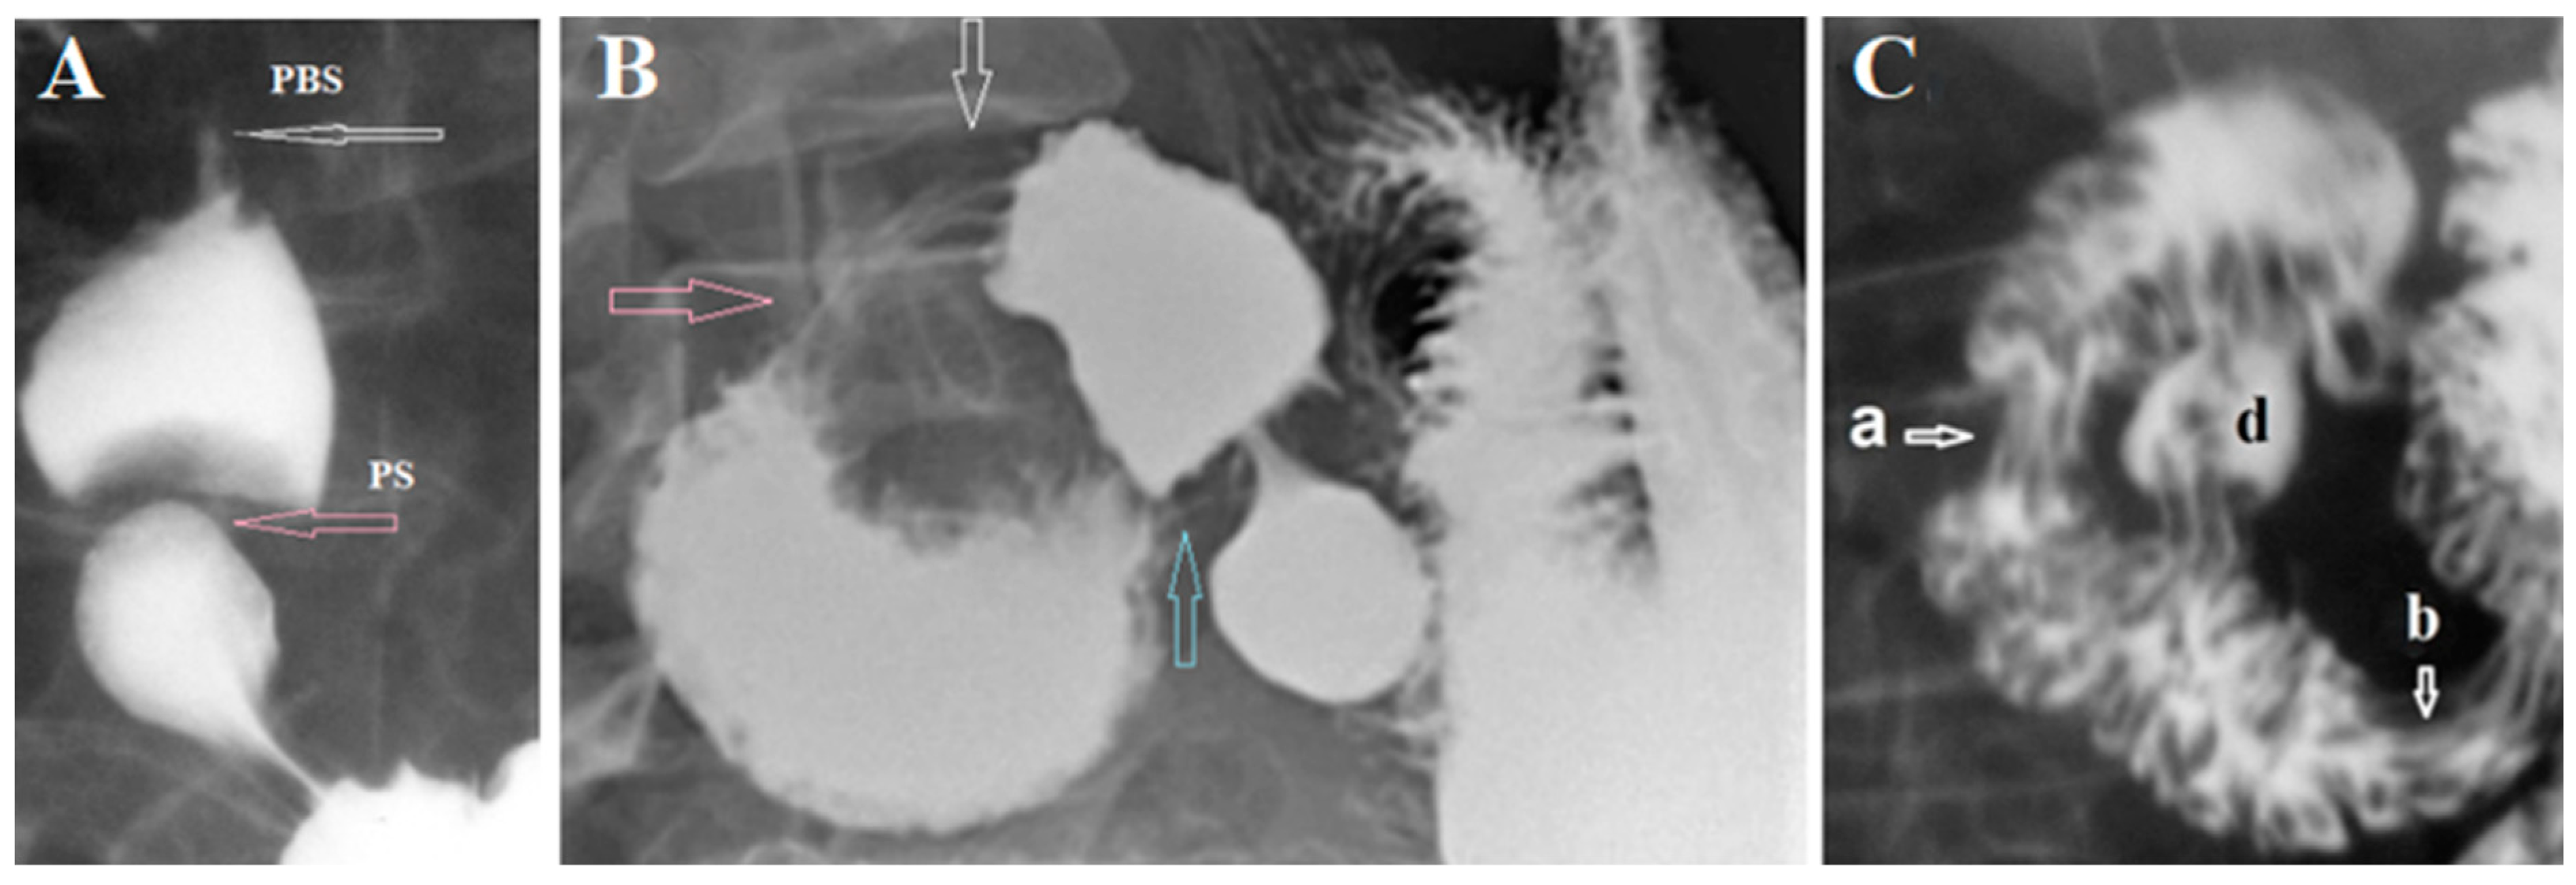

Ever since Professor Carl von Rokitansky (1842) advanced the vascular hypothesis it is believed that obstruction of the 3rd part of the duodenum is caused by intestinal compression in the aortomesenteric angle (AMA). The abdominal aorta is located near the middle of the vertebra

(Figure 2a-b) Its width is approximately 2 cm, and the width of the superior mesenteric artery (SMA) is 0.5 cm. The length of the constriction that these vessels can create cannot exceed 1 cm. I measured the distance from proximal points the sharp contraction in the 3rd part of the duodenum to the location of the SMA, i.e., up to the middle of the 3rd lumbar vertebra (L-3) on 35 radiographs, CT, and MRI, published in PubMed and PMC. On radiographs, all the values are greater than the real ones. We calculated the true value by multiplying the value measured on the radiograph by the projection increase factor. It is equal to the ratio of the true height of the first lumbar vertebra (2.2 cm in adults) to the value of its image on the radiograph. When analyzing CT and MRI, the coefficient is equal to the ratio of the true diameter of the abdominal aorta (2 cm) to the value of its image on the scan. In 29 (83%) cases on X-ray examination or on CT and MRI, the length of the narrowed segment of the duodenum ranged from 2.5 to 4.6 cm (3.30 ± 0.15 cm) and always started a few centimeters to the right of L-3 (

Figure 2a-d) [

1,

3,

6,

7].

Only in 6 (17%) of 35 cases where the length of the narrowed segment of the could be measured, it looked short, since the place of obstruction was near the midline of the vertebra and its length was within 1 cm. However, as seen in

Figure 2 e, the narrowed segment of the duodenum can be located to the left of the midline of the vertebra, which is confirmed by Ochsner’s observations during surgery. Secondly, the X-ray can show the moment opening of the Ochsner’s sphincter, which happens when there is high pressure above it

(Figure 3).

From the analysis of radiological studies, it follows that in all cases, the contraction of the Ochsner sphincter, and not the compression of the duodenum in the AMA, is the cause of the so called SMAS.

А) All authors, referring to the article by Neri et al. [

10], believe that the AMA value less than 25 ° is an important diagnostic feature of SMAS. However, the study, to which everyone refers, was carried out with numerous violations that do not allow us to consider its results reliable, that is, scientific. Studies with the AMA <25 ° were initially selected. No justification for the choice of this figure is provided. There are no characteristics of 50 healthy subjects (control group). The authors did not measure AMA for persons with different BMIs. Therefore, they had no reason to report normal boundaries at all. «The US detected reduced angles <25 ° in 29 of the 950 subjects (3.05%). X-ray with barium (

Figure 4a) revealed compression on the third segment of the duodenum in 28 of 29 patients during the symptomatic period and in nine of 29 during the symptom-free interval» [

10]. On the radiograph

(Figure 4a), which Neri et al presented as the most demonstrative of 29, there are no signs of obstruction because neither the stomach nor the duodenum is dilated. Therefore, this case does not have the main features of SMAS. Secondly, the narrowing on this x-ray, that begins to the right of the vertebra has nothing to do with AMA. It corresponds to the contraction of the Ochsner sphincter. This is confirmed by a similar observation by Eisenberg [

11]

(Figure 4b-c). Thus, this radiograph does not correspond to the concept of SMAS and as well as all the conclusions of the article by Neri et al it is a falsification of the facts for confirming the invented limit of the AMA norm - 25°. So, for example, it states: “The aortomesenteric angle is normally 25–60° {[2,3,6,7,10-12]} and the mean aortomesenteric distance of 10–28 mm {[1-3,6,7,10-12]}. Subjects presenting an angle <25° and aortomesenteric distance <8-10 mm may be affected by SMA syndrome” [